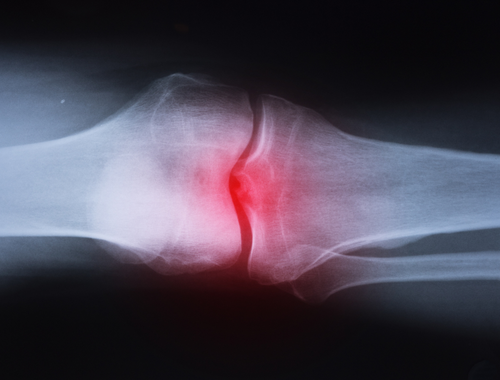

Symptoms present initially as pain and swelling at the site of infection and fever. Erythema or reddening of the skin surrounding the bone may follow, then necrosis of the surrounding tissue and the formation of purulent wounds and ulcers.

Many symptoms of septic arthritis are common to sterile arthritis, including intense joint pain, difficulty moving or using the affected limb, and redness or swelling at the site of infection. Septic arthritis also presents symptoms of bacterial infection, including fever, chills, and tachycardia.

Osteomyelitis and septic arthritis both present nonspecific symptoms of joint pain and fever. Purulent wounds or ulcers are frequently symptomatic of osteomyelitis but not septic arthritis.